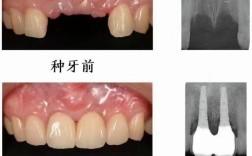

种植牙对骨量的要求远高于传统修复方式,牙齿缺失后,牙槽骨会因失去咀嚼刺激而逐渐吸收萎缩,尤其是缺牙时间较长、牙周病严重或外伤导致的骨缺损,骨量往往无法满足种植体的植入需求(通常需要种植体长度至少8-10mm,周围骨宽度至少3-4mm),20年前,由于术前检查手段有限,医生主要依赖普通X光片(如根尖片、曲面断层片)评估骨量,这些二维影像无法精确显示骨量的三维形态,容易低估骨缺损程度,导致术中发现骨量不足时不得不临时植骨。

长期缺牙导致的严重骨吸收

后牙缺失数年甚至十年以上,牙槽骨因缺乏咀嚼刺激而垂直向和水平向吸收严重,剩余骨高度不足8mm、宽度不足5mm,此时直接种植可能导致种植体穿入上颌窦、下颌管等重要解剖结构,或因骨覆盖不足导致松动,医生需先进行“块状植骨”或“骨劈开术”,通过自体骨或骨替代材料重建骨量,待3-6个月骨愈合后再二期植入种植体。

牙周病活动期的骨缺损

慢性牙周病会导致牙槽骨吸收形成“骨下袋”,牙齿松动脱落,若患者在牙周病未控制好时就进行种植,可能因炎症导致种植体周围炎,最终失败,20年前的流程通常是:先进行牙周基础治疗(洁治、刮治),对骨缺损区域进行植骨引导再生,控制炎症半年后再评估种植条件,若骨量仍不足,需再次植骨,等待骨结合完成后再种植。